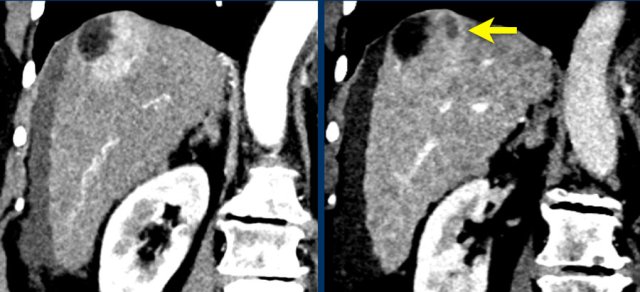

The images show an only mild rim-like arterially enhancing lesion in segment V with washout.

A linear area of hypoenhancement is seen extending from the mass which is suspicious of tumor in vein (yellow arrow).

Since we are not absolutely sure that it is a tumor thrombus, we cannot categorize this as LR-TIV.

A follow up CT was done, showing severe progression of the tumor as well as vascular involvement of the anterior right portal vein (white arrow).

Now we are sure of tumor invasion in the portal vein.

The coronal images shows a large lesion treated with TACE with residual areas of mild arterial enhancement and washout due to untreated supply via a phrenic artery (yellow arrow): LRTR-viable.

Continue with the axial image ...

Note there is irregularity of the peritoneal fat anteriorly due to capsular rupture (arrow).